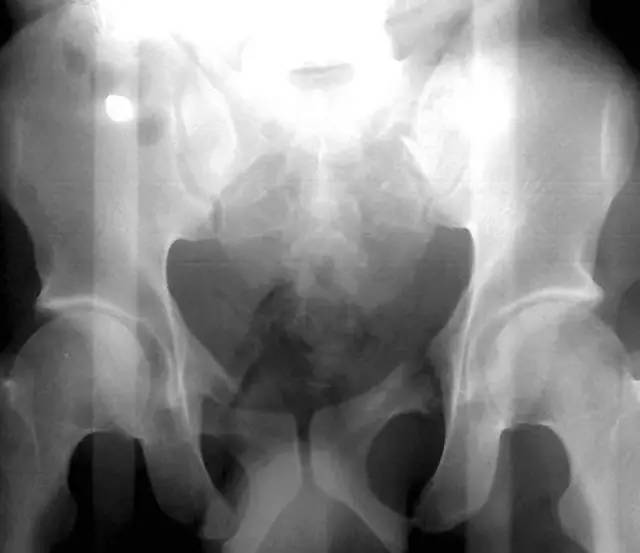

(1)Malgaigne 骨折

指垂直不稳定骨盆骨折,骨折累及双侧耻骨支、骶髂关节或者骶骨。